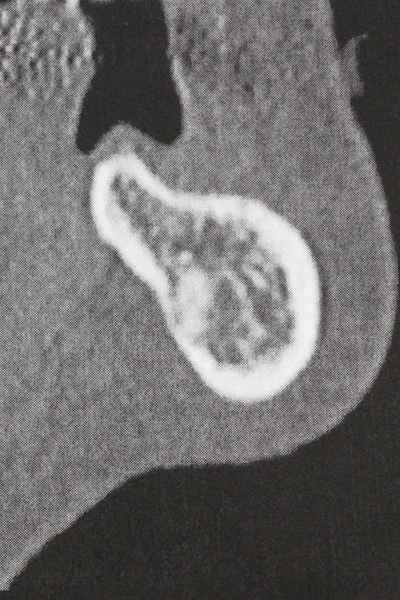

cazione: rialzo del seno

La preparazione della finestra laterale durante un rialzo del pavimento sinusale esterno è complicata, in particolare per gli implantologi con poca esperienza chirurgica. La rimozione della copertura ossea del seno senza danneggiare la membrana schneideriana sottostante è solo una parte dell'operazione: dopo aver stabilito un accesso adeguato, la membrana interna del seno deve essere spostata con cautela per far spazio ai materiali di accrescimento o agli impianti. La piezochirurgia è utile per questa indicazione in due modi: è possibile utilizzare gli strumenti diamantati per l'ablazione selettiva dell'osso e, se la procedura viene eseguita con precisione, la membrana mucosa sottostante rimane intatta. Le frequenze ultrasoniche permettono anche la separazione della membrana mucosa senza complicanze: le frequenze vengono trasmesse nello spazio compreso tra la membrana mucosa e il pavimento sinusale mediante degli speciali raccordi smussati (Cassetta, Ricci et al. 2012, Pereira, Gealh et al. 2014) (Rickert, Vissink et al. 2013). Di conseguenza, non sorprende che le rivisitazioni attuali del rialzo del pavimento sinusale esterno valutino positivamente l'utilizzo dei dispositivi piezoelettrici, delle superfici non lisce degli impianti e dei materiali di riempimento dell'osso (Wallace, Tarnow et al. 2012).